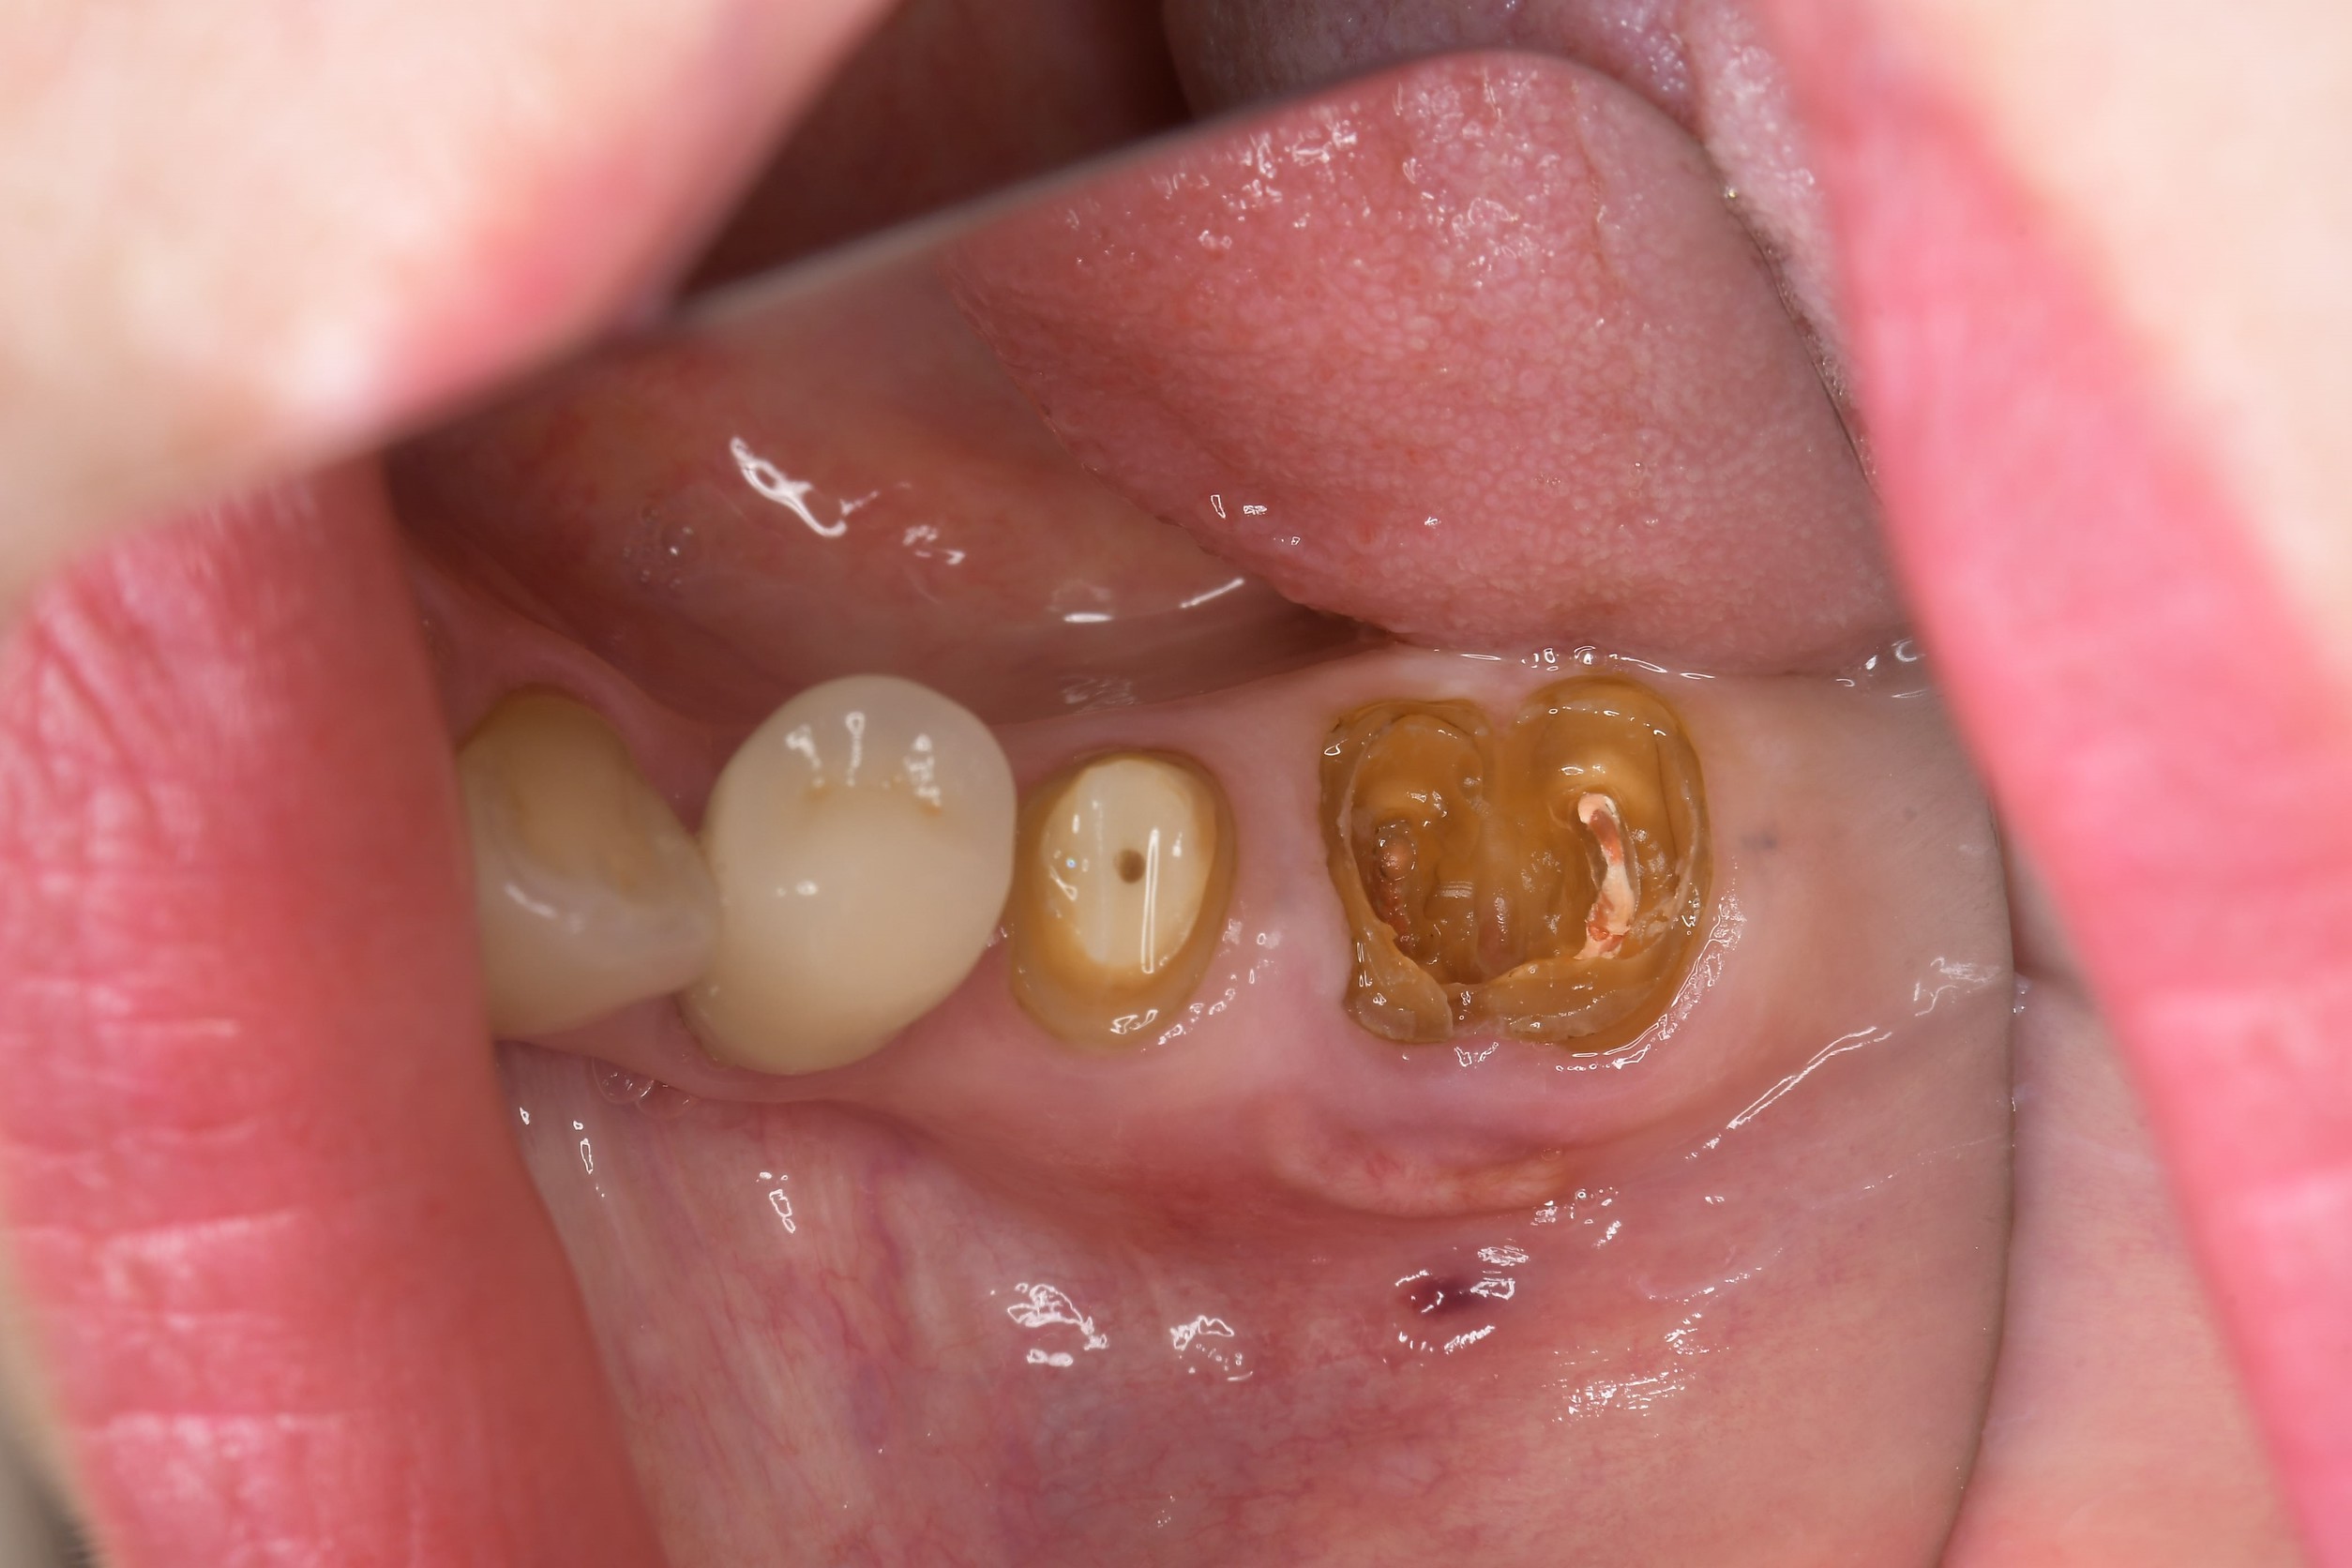

当初は「左下奥歯の違和感」を主訴に来院されました。当院の歯内療法専門医が精密な診断を行ったところ、左下5番(第2小臼歯)に「破折」が認められ、残念ながら抜歯適応との診断となりました。

その後、経過観察中に今度はその奥の左下6番(第1大臼歯)の歯ぐきに「フィステル(おできのような腫れ)」が出現。被せ物を外して内部を確認したところ、過去の根管治療の影響と思われる「穿孔」が確認され、こちらも保存不可という厳しい状況でした。

2. ご来院時の状態と診断

精密検査の結果、以下のことが明らかになりました。

・左下5番: 歯根破折。

・左下6番: 根管内の穿孔。